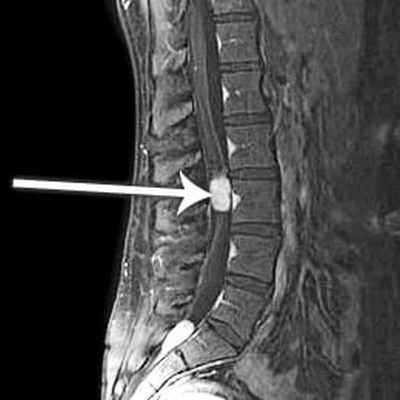

(Слева) На схеме сагиттального среза показана многоуровневая миксопапиллярная эпендимома конского хвоста. Опухоль хорошо васкуляризирована, с признаками старых внутриопухолевых кровоизлияний и свежего субарахноидального кровоизлияния вдоль дорзальной поверхности конуса спинного мозга. Медленный рост опухоли приводит к расширению спинномозгового канала и ремоделированию задней покровной пластинки тела позвонка.

(Справа) Фронтальный срез, Т1-ВИ: четко ограниченное интрадуральное экстрамедуллярное образование поясничного отдела позвоночника. Образование характеризуется преимущественно изоинтенсивным по отношению к спинному мозгу и корешкам сигналом. Практические 70% опухолей терминальной нити — это эпендимомы, в основном миксопапиллярного типа. (Слева) Сагиттальный срез, Т2-ВИ: распространенная интрадуральная опухоль, деформирующая конус спинного мозга и конский хвост. МЭ уникальны тем, что они обладают способностью накапливать внутриклеточно и в периваскулярных пространствах муцин, который дает гиперинтенсивность сигнала в Т1/Т2-режимах.

(Справа) Сагиттальный срез, Т1-ВИ с КУ: яркое и гомогенное усиление сигнала опухоли. Обратите внимание на наличие множества интрадуральных отсевов опухоли. Более мелкие опухоли обычно смещают корешки конского хвоста, тогда как более крупные сдавливают или полностью окружают их.